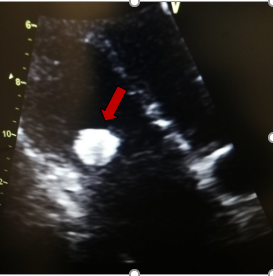

Τα σαρκώματα είναι τα πιο συνήθη από τα κακοήθη πρωτοπαθή νεοπλάσματα της καρδιάς. Η τυπική ηλικία εμφάνισης είναι μεταξύ 40 και 50 ετών. Στην ηχοκαρδιογραφία, εμφανίζονται ως μία μάζα με ευρεία βάση και ανομοιογενή ηχογένεια, συνήθως στο δεξιό κόλπο. Οι υπόηχες περιοχές εντός του όγκου αντιστοιχούν σε εστίες νέκρωσης του όγκου.

Εκτός από το δεξιό κόλπο που είναι η συχνότερη εντόπιση, μπορούν επίσης να εμφανιστούν σε οποιαδήποτε καρδιακή κοιλότητα και συχνά προσβάλλουν το περικάρδιο, με αποτέλεσμα την περικαρδιακή συλλογή και το θωρακικό άλγος από ερεθισμό του περικαρδίου. Όταν βρίσκονται σε μία δεξιά καρδιακή κοιλότητα, μπορούν να προκαλέσουν διαταραχή στη λειτουργία της τριγλώχινας βαλβίδας, να προκαλέσουν κλινικές εκδηλώσεις δεξιάς καρδιακής ανεπάρκειας και / ή να εμφανίσουν μεταστάσεις στους πνεύμονες. Η διαφορική διάγνωση είναι με το μύξωμα. Σε αντίθεση με τα μυξώματα, τα σαρκώματα δεν έχουν μίσχο. Τα σαρκώματα τείνουν να έχουν ταχεία ανάπτυξη, παρακωλύοντας τη ροή του αίματος. Η αντιμετώπιση με χειρουργική εκτομή του όγκου είναι εφικτή σε μερικές περιπτώσεις. Οι κακοήθεις πρωτοπαθείς καρδιακοί όγκοι είναι εξαιρετικά σπάνιοι. Σε σχεδόν όλες τις περιπτώσεις πρόκειται για σαρκώματα, με το αγγειοσάρκωμα να είναι το πιο σύνηθες μεταξύ αυτών. Τα σαρκώματα μπορούν να εμφανιστούν σε οποιαδήποτε καρδιακή κοιλότητα, αλλά βρίσκονται συχνότερα στον δεξιό ή τον αριστερό κόλπο. Οι κακοήθεις καρδιακοί όγκοι έχουν κακή πρόγνωση.